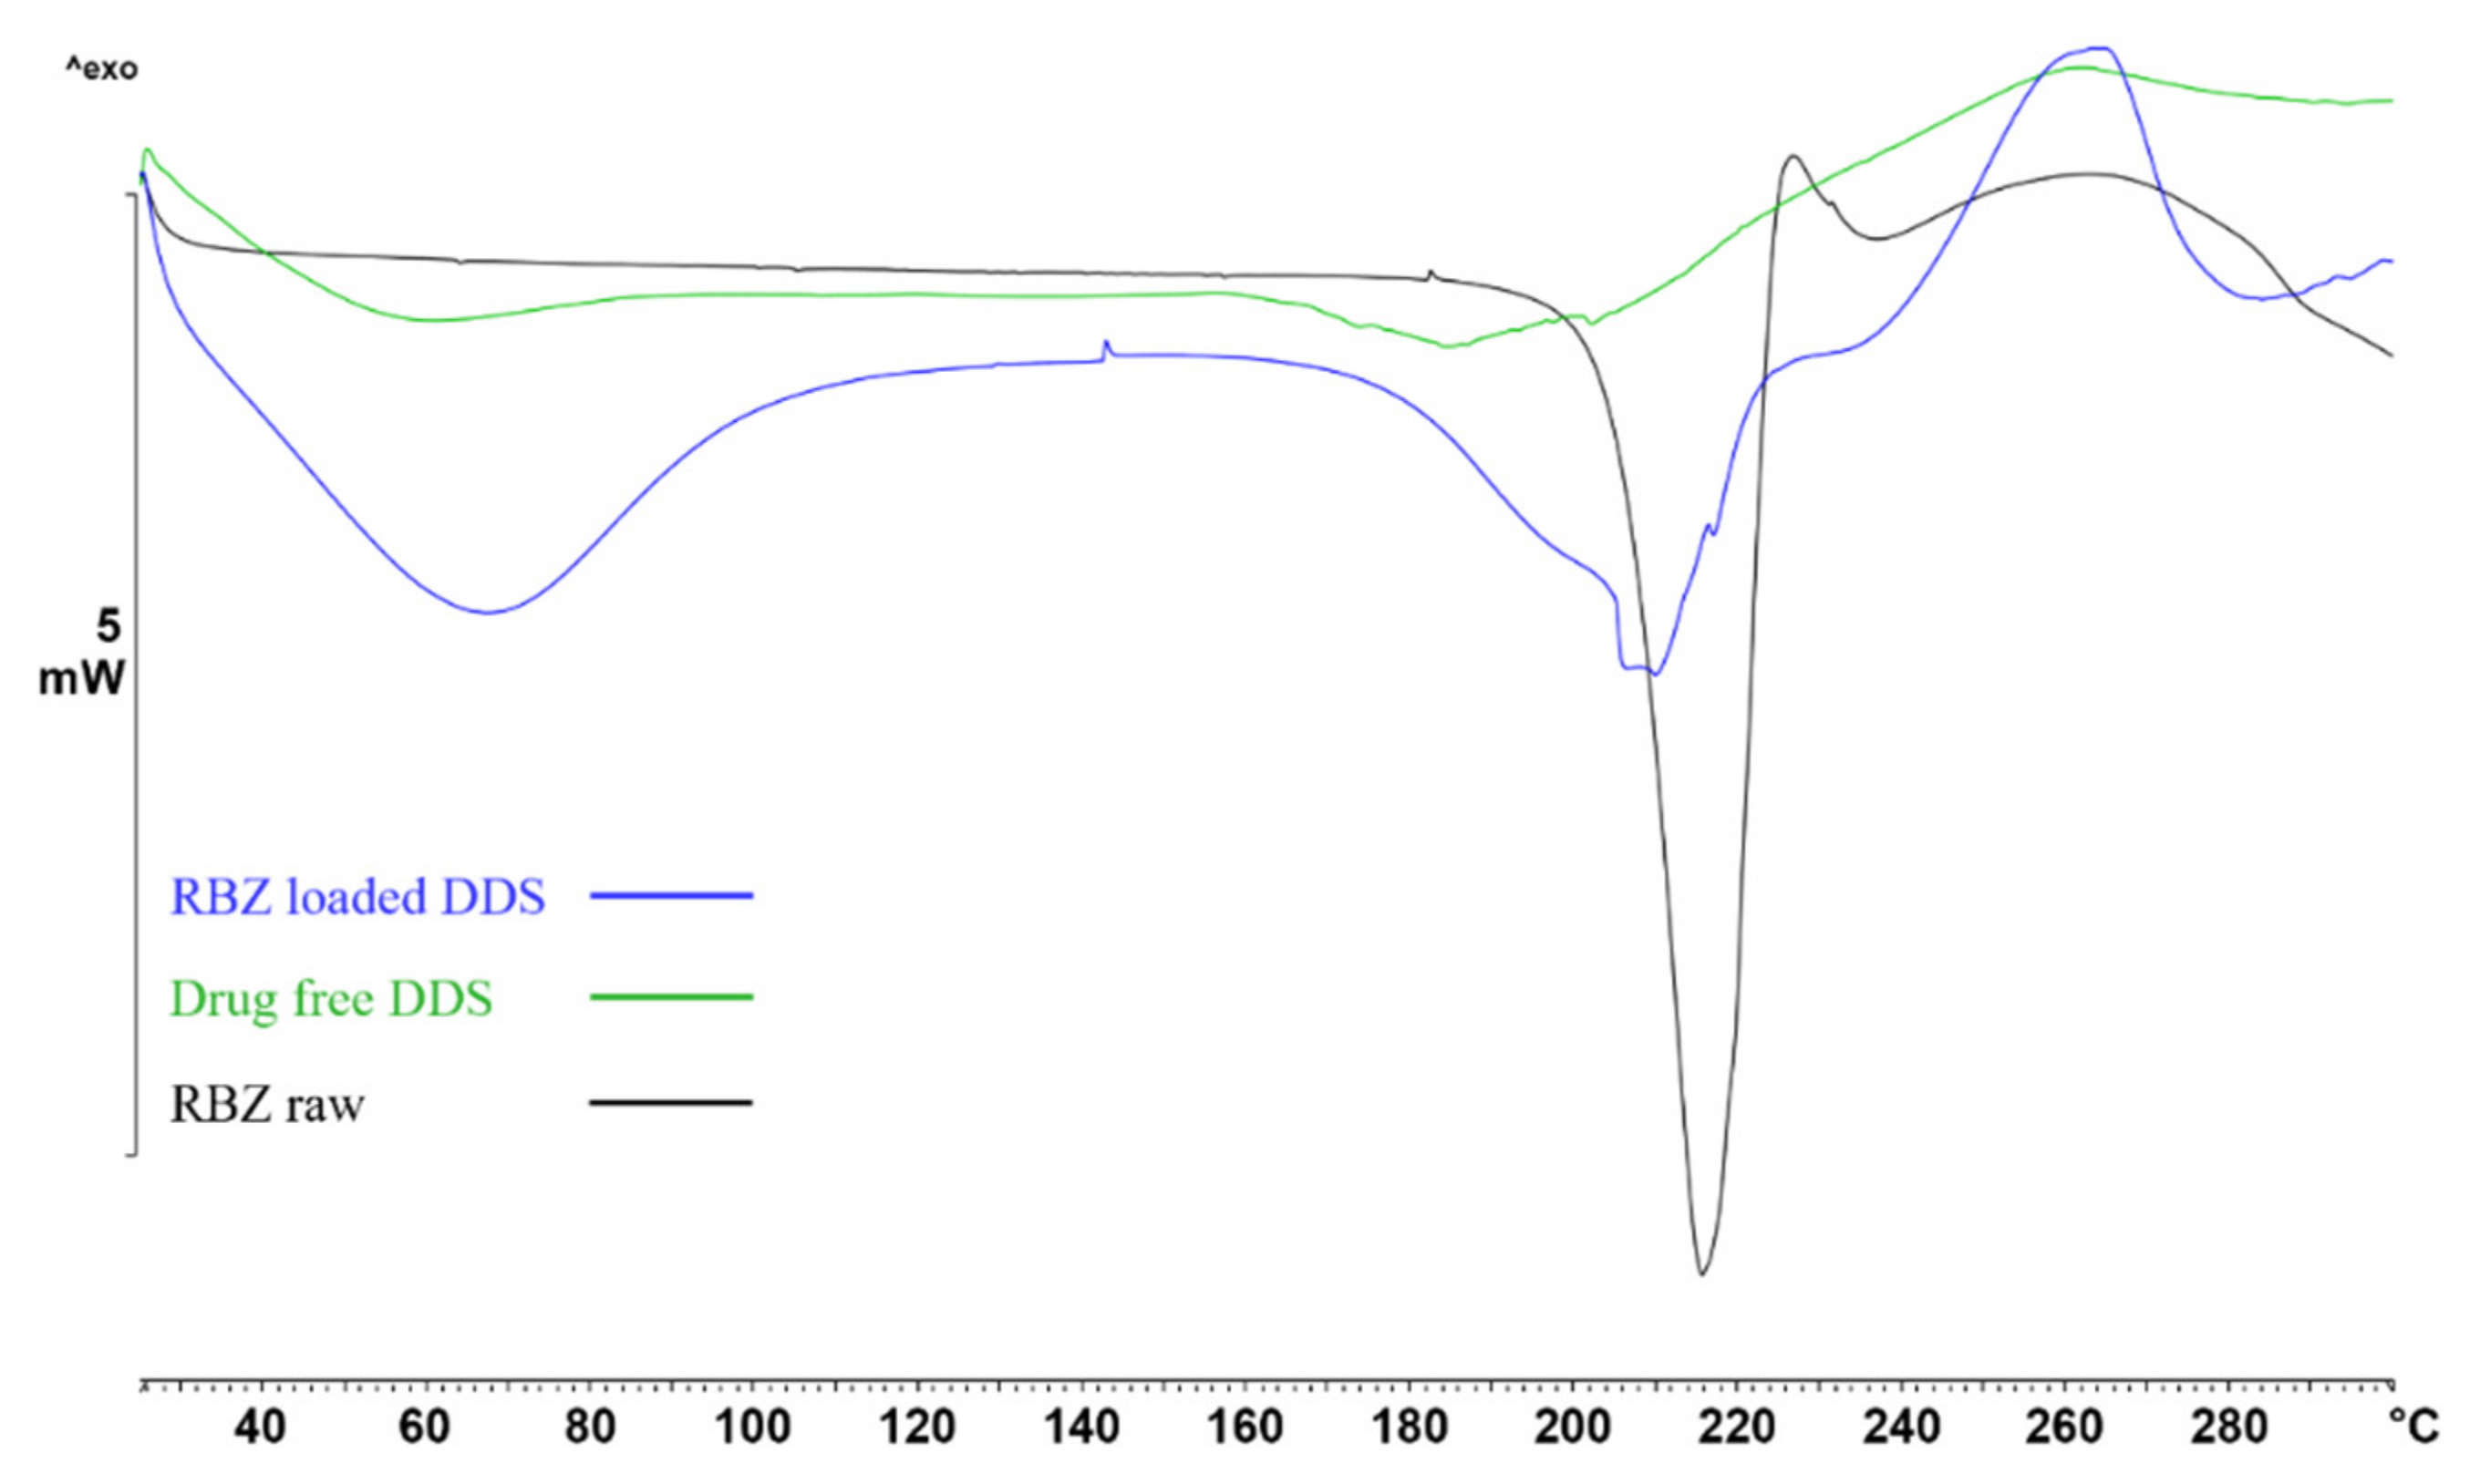

2.4. FT-IR and DSC Analysis

4.2.4. DSC Thermal Analysis